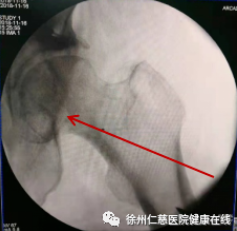

天玑机器人对髋关节精准定位、精准钻孔

钻孔减压术可以减轻股骨头颈内高压,改善血液循环,减轻骨髓水肿,阻止股骨头坏死的进一步发展。在天玑机器人辅助下,精准定位聚焦病灶,通过骨科机器人机械臂的引导,将导针准确打入坏死病灶进行减压,这样能有效改善股骨头内部的血液循环。钻孔减压+体外冲击波+激光磁综合治疗股骨头坏死,创伤较小、切口小,手术风险小、并发症少。